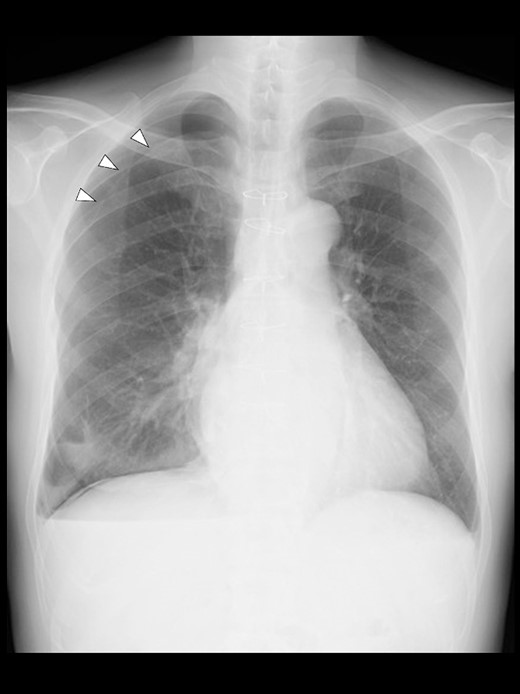

Even though the patient did not receive supplemental oxygen in the ward, SpO2 remained at 98%. Chest radiographs were not taken on the day of surgery. However, a chest radiograph taken in the upright position on postoperative Day (POD) 1 revealed a pneumothorax on the right side (Fig. 2), although he had no respiratory symptoms. Radiographs on PODs 2 and 3 revealed the pneumothorax remaining unchanged (Fig. 3). The patient was discharged from the hospital on POD 3 without any respiratory symptoms. A chest radiograph taken on POD 19 showed no remaining pneumothorax.

A chest radiograph in the upright position on POD 1 showing a right pneumothorax (arrowheads).